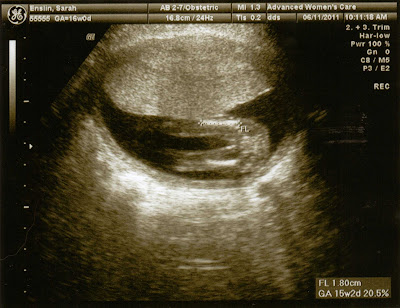

Dancing baby Grace in 4D at 16 weeks

This came from the ultrasound done on 6.11.11

I can't help but think she knew she was putting on a show. Looks like she's already a little show off. Let's hope her coordination and dancing skills are better than her mama's if she decides to pursue dancing, cheerleading (please god no), or gymnastics in the future.

But here it is, Dancing Gracie...